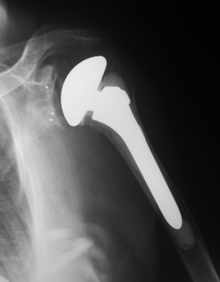

Liegen eine Arthrose des Schultergelenkes und ein großer Riss der Rotatorenmanschette vor und ist wegen der Schmerzen in der Schulter und der Schwäche im Arm eine Operation erforderlich, so hat sich die inverse Prothese bewährt. Dabei werden Kugel und Pfanne des Gelenkes vertauscht, um den gesunden Muskeln die Möglichkeit zu geben, die Funktion der gerissenen Muskeln zu ersetzen. Die Nachbehandlung gleicht der „normalen“ Endoprothese der Schulter.